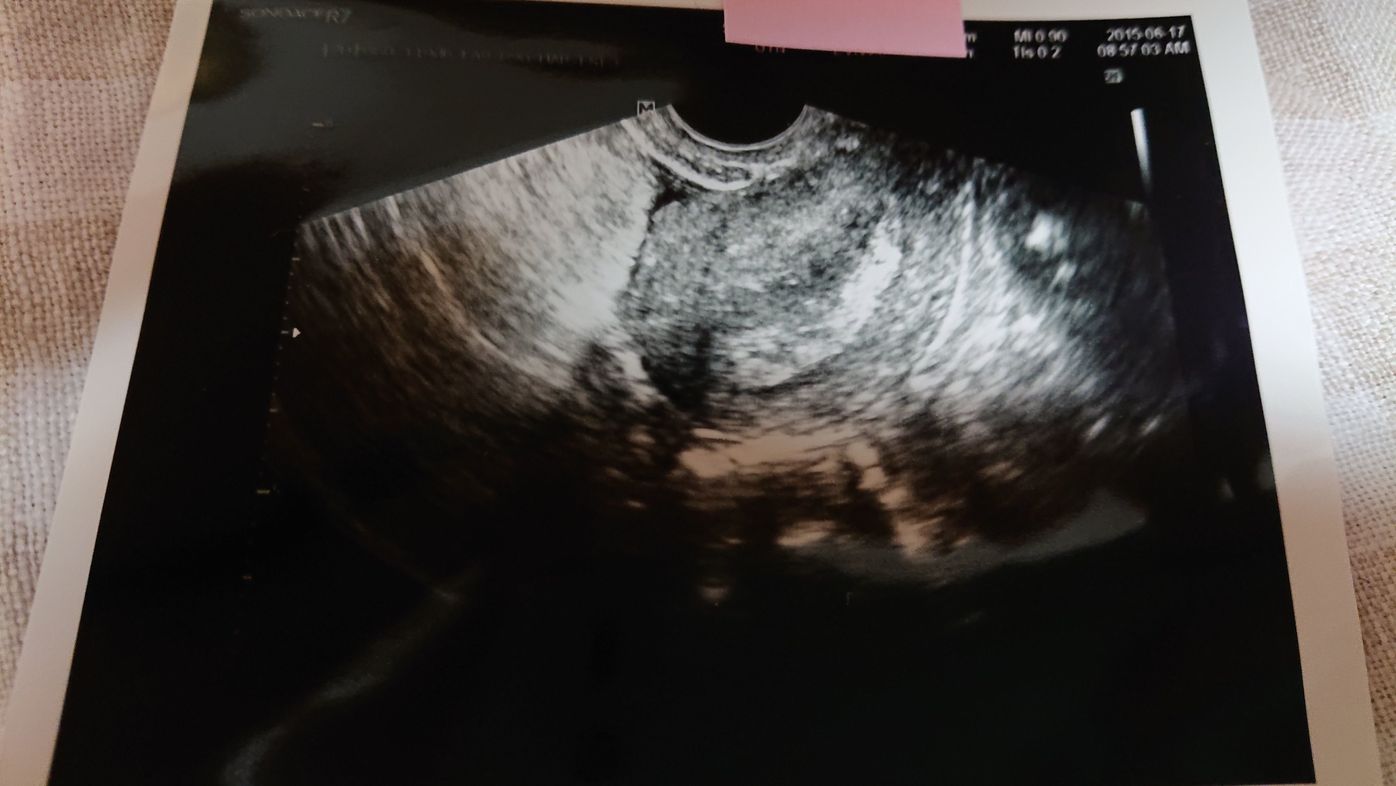

妊娠4週目のエコー写真 胎芽や胎嚢 初期症状や流産のこと 妊娠初期 All About

妊娠4週目 4w0d 6d のエコー写真とエピソード 妊娠2ヶ月 Cozre コズレ 子育てマガジン